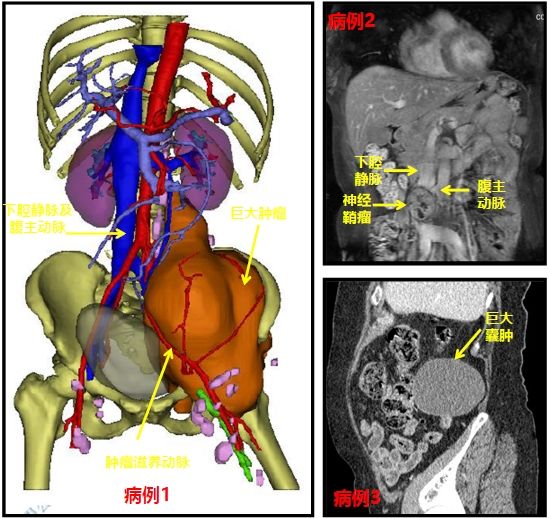

近日,我科收治一男性患者,该病人于外院诊断为肾囊肿,拟入我科行手术治疗,要求刘川教授亲自主刀。患者入院后,我院CT检查提示马蹄肾、双

新一年开启新希望,新空白承载新梦想。春节假期后第一天,我院门诊门庭若市,一早血管外科唐博副教授连续接诊了三位腹部包块患者。第一位患